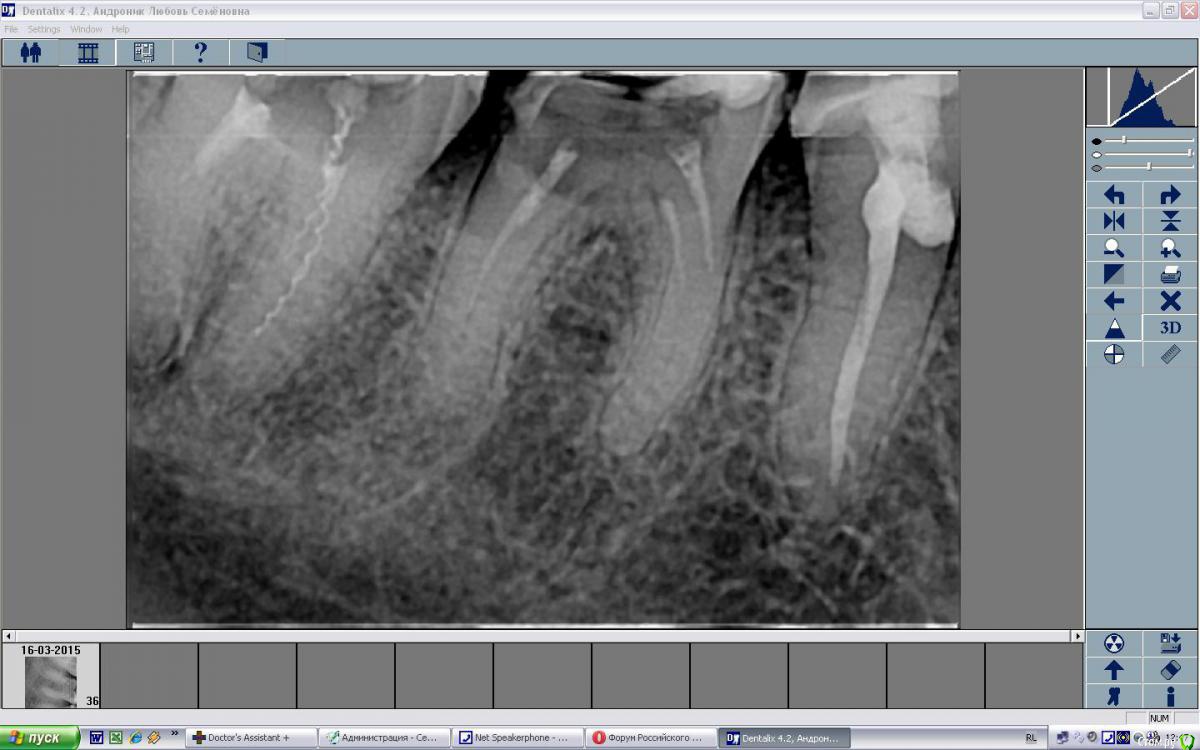

SatoSan Опубликовано 18 марта, 2015 Поделиться Опубликовано 18 марта, 2015 Такое эндо делает соседняя клиника очень даже не дешего...Если бы Колян из сериала "Реальные пацаны" был бы стоматологом, то при виде этого он бы сразу сказал: "Ну как так то???"PS: 35; 36; 37 все лечены там Ссылка на комментарий

SatoSan Опубликовано 18 марта, 2015 Автор Поделиться Опубликовано 18 марта, 2015 вообще отказался в работе с канал-м чтобы не оставить его там.Дело вообщем-то не в каналонаполнителе, а нормальной инструментации каналов! Если 20м файлом "поелозить" по стенкам и пытаться потом туда залезть каналонаполнителем то результат вполне предсказуем.... 1 Ссылка на комментарий

SatoSan Опубликовано 22 марта, 2015 Автор Поделиться Опубликовано 22 марта, 2015 (изменено) А к вам пришли с каким вопросом?Жалоб было множество: начиная от головной боли, боли в области нижней челюсти слева и заканчивая положительной перкуссией 37. Под удаленной мной пломбой на 37 была обнаружена ватка с запахом крезофена. Со слов пациента зуб был лечен 2 года назад. Опять же с её слов она обратилась с этой болью к своему доктору, соотвественно пломба с 36 была удалена каналы не распломбированы и полоскание назанчено.... Изменено 22 марта, 2015 пользователем SatoSan Ссылка на комментарий